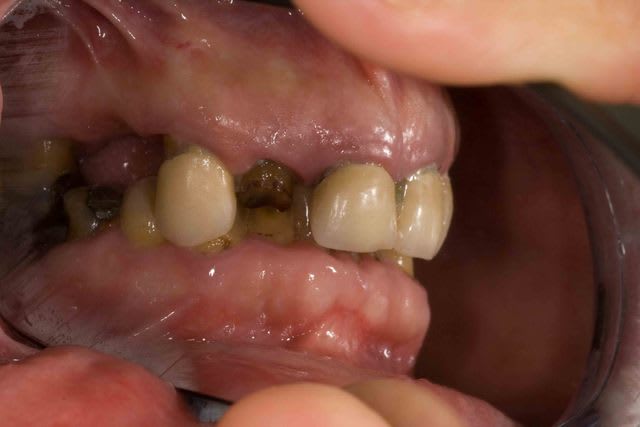

Pour l'egression des dents mandibulaire le patient ne voulait SURTOUT pas toucher au dents encore "saines" .

"Chaques fois qu'on ma touché une dent j'ai eu un probleme donc si elles n'ont rien touchez les pas svp "dixit le patient. En augmentant la DV de 4 mm j'ai pu eviter les meulages.

Le probleme c'est que maintenant il ne les trouvent pas belles et veut les blanchir/meuler... Sont jamais content les patients.

Pourquoi blanche : toujours selon le patient . "Dr j'ai eu les dents pourris toutes ma vie, aucun dentiste n'a voulu me soigner . Si vous me faites quelque chose je veux que se soit blanc" Amen